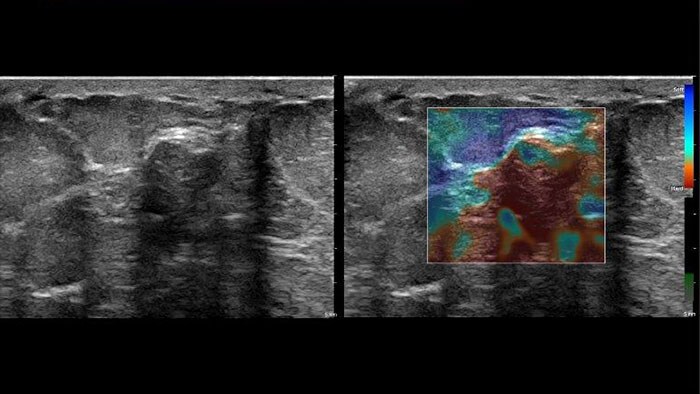

US Q-App Elastography Quantification (EQ)*

Explore new tissue stiffness measurements

US Q-App Elastography Quantification (EQ)* allows you to strain elastography quantification of tissue deformation based on an elastogram. Calculate and display the strain rate and total strain, size compare between two ROIs, and strain ratio; results may be appended to patient reports.

Benefits

- Thumbnail display of frames.

- Size comparison between two ROIs.

- Strain ratio calculation.

- Calculation and display of strain rate and total strain.

- Graphical display of strain ratios with parametric imaging.

- Append to patient exam.

- Compatible with Philips EPIQ , Affiniti and iU22 systems using Elastography mode.

* Not available for sale in the US.